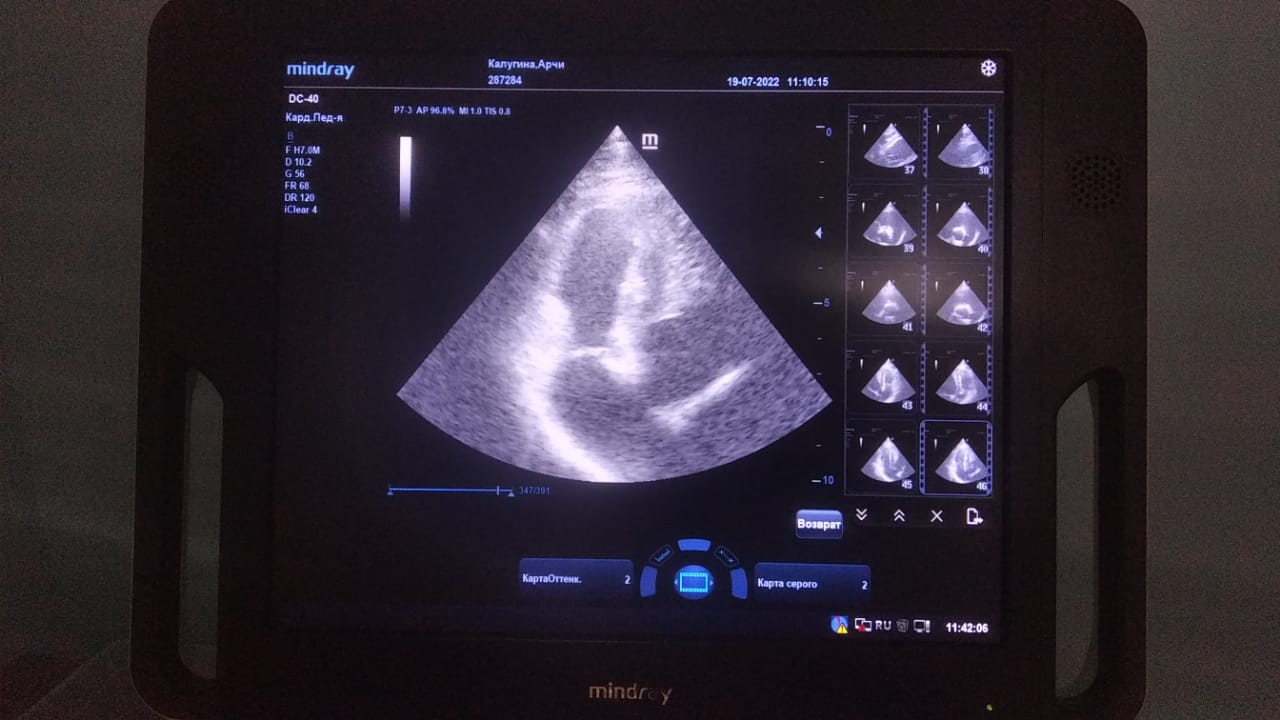

Анализы Арчи. Сердца и легких

Вложения

IMG-20220719-WA0100.jpg

IMG-20220719-WA0102.jpg

IMG-20220719-WA0104.jpg

IMG-20220719-WA0103.jpg

IMG-20220719-WA0105.jpg

Продолжение.

IMG-20220719-WA0097.jpg

IMG-20220719-WA0096.jpg

IMG-20220719-WA0099.jpg

IMG-20220719-WA0098.jpg

IMG-20220719-WA0101.jpg